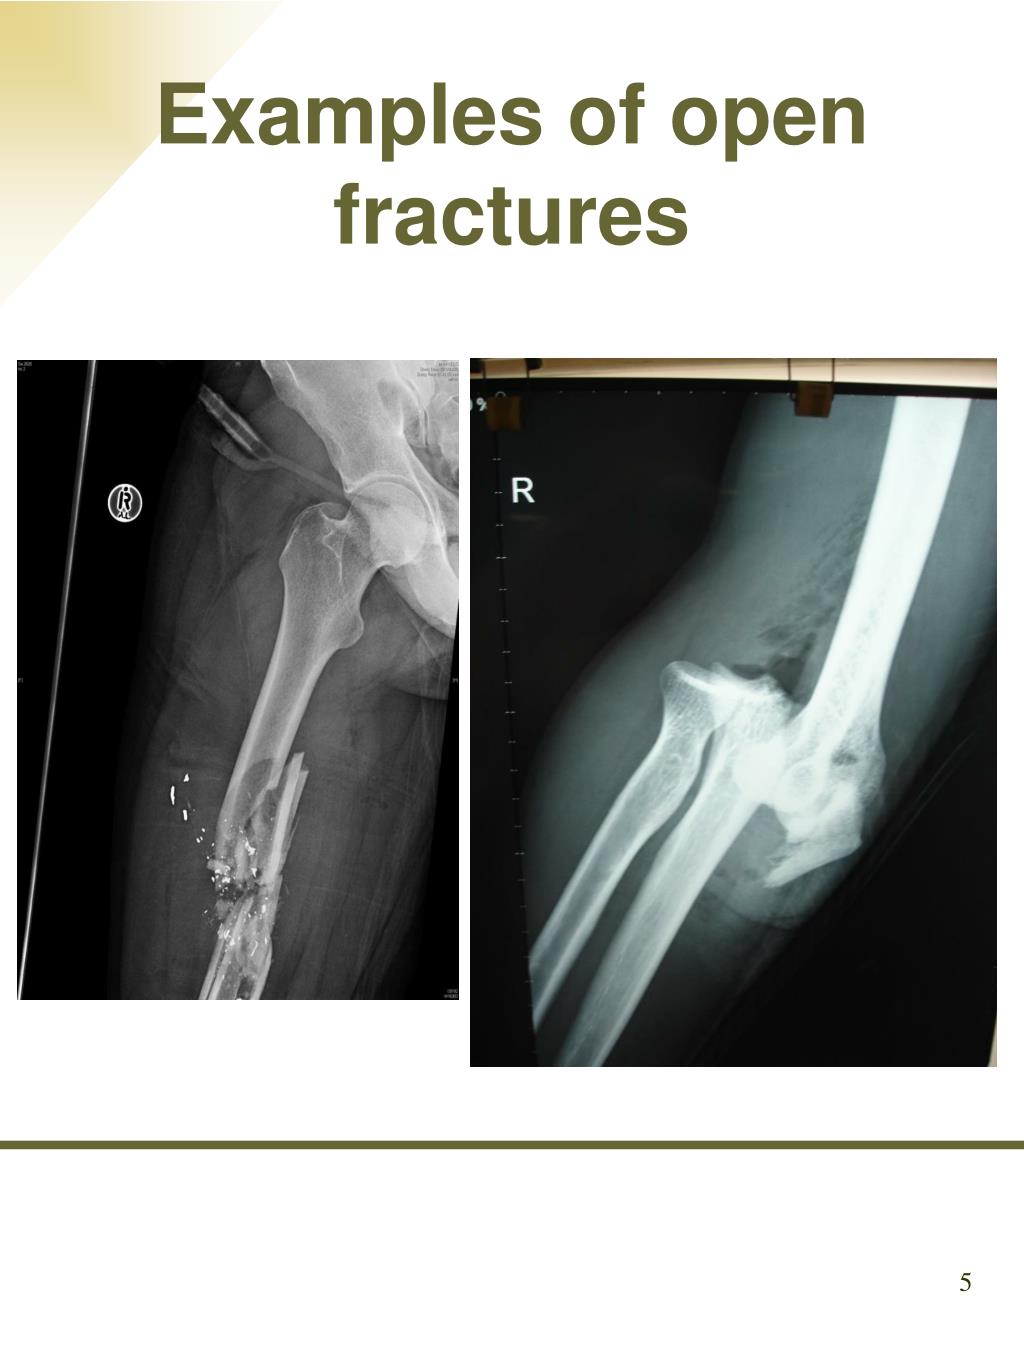

5. Examples of open fractures 5